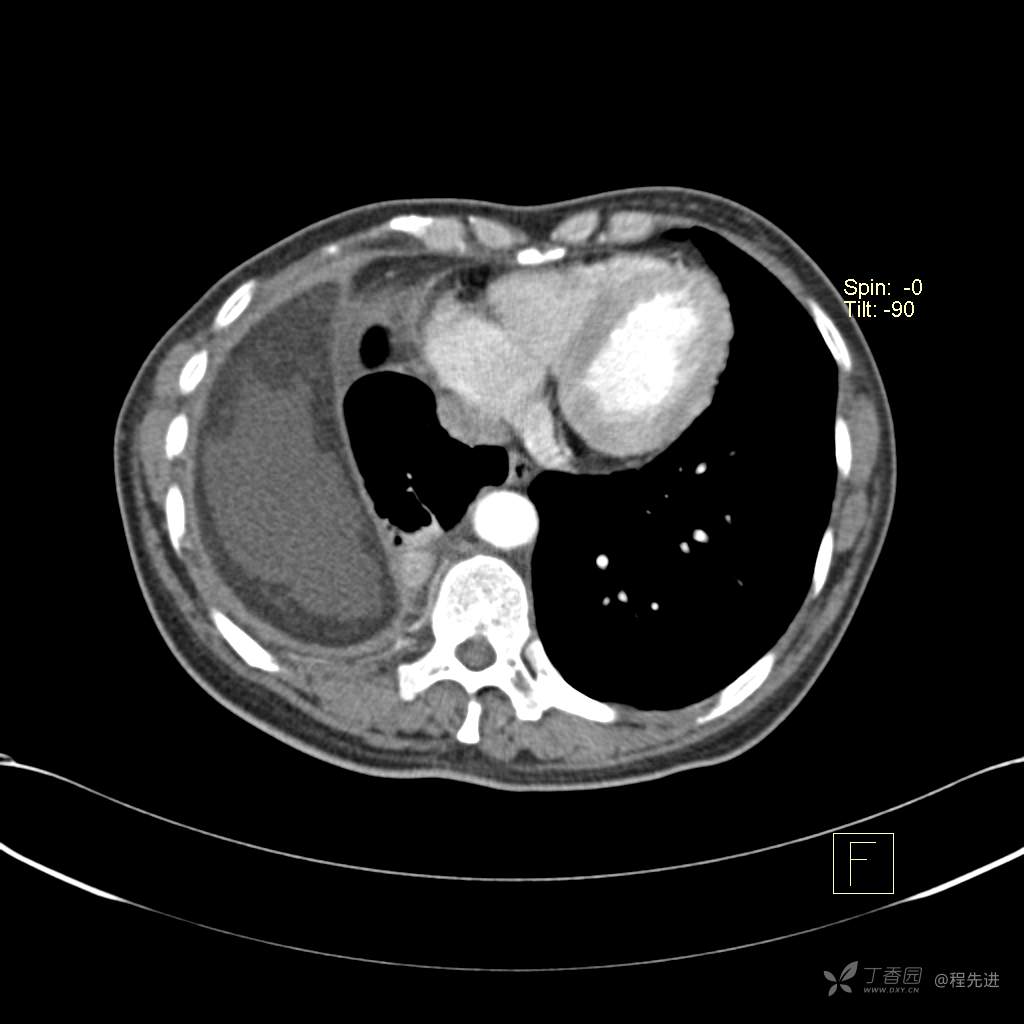

患者性别:女

患者年龄:51岁

简要病史:胸闷半年